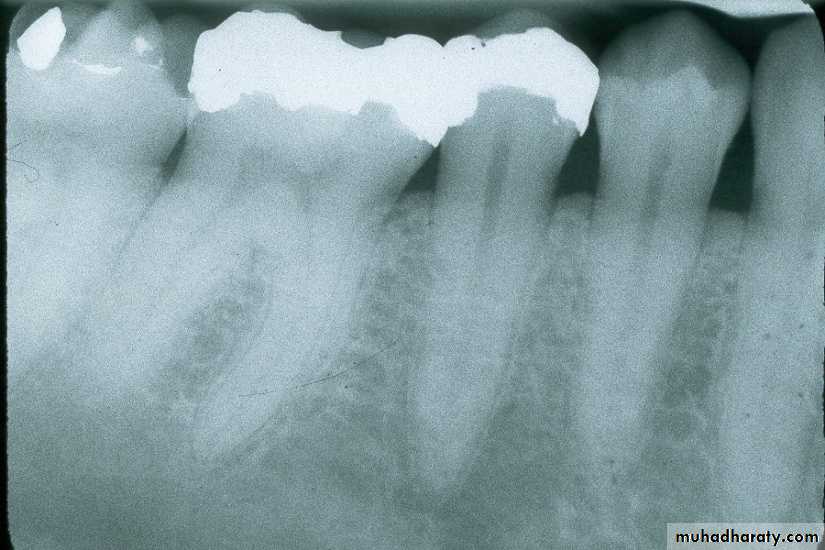

Maxillary Molar

film centered on second molarfilm in center of palate

film equidistant from palatal surfaces of teeth (red arrows); this opens contacts between the teeth.

Some patients, especially larger individuals, will have longer than normal teeth. With the normal positioning of the film and alignment of the beam, the apices of the teeth will be above the edge of the film (not visible or “cut off”) as in the illustration above left.

To compensate for this, increase the angle of the beam and raise the PID slightly (illustration above right). You are purposely foreshortening the image.

top edge of PID above ring